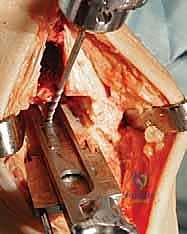

3. إزالة الأسطح التالفة (تحضير العظام)

باستخدام أدوات جراحية دقيقة وموجهات خاصة، يتم إزالة الغضاريف التالفة وجزء رقيق جداً من العظام المريضة من نهايتي عظمة الظنبوب وعظمة الكاحل (Talus). يتم تشكيل العظام بدقة لتتطابق تماماً مع شكل أجزاء المفصل الصناعي.